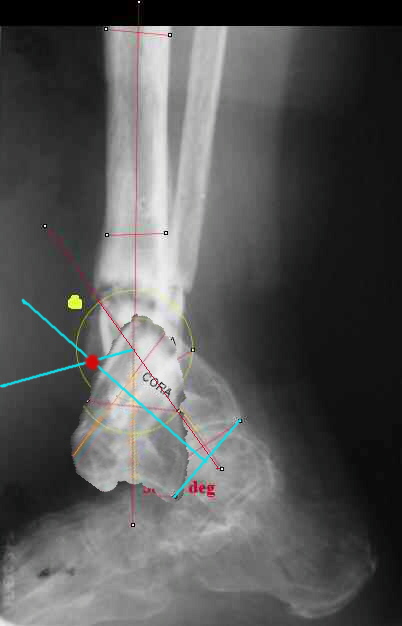

TDVC> I played with your image using some orthopedic software

TDVC> we have been developing for digital image analysis.

TDVC> a correction around the CORA through the old # will restore

TDVC> alignment without much translation.

Maybe my "embedded software" is obsolete but it hints me to place hinges at the yellow point - this must result with alignment and some lengthening without translation. What do you think?

I think that if you locate the hinge at that site and then you rotate the foot about this point with out distraction you will be perfectly lined up. If you distract in the axis of the proximal tibia then rotate, it should still work (the hinge should still be located in the mid tibial axis). But, if you distract out of that axis then you will get translation. Does that make sense?

I looked at your image. I presume your yellow marker is the hinge axis? I think this should be at the CORA.